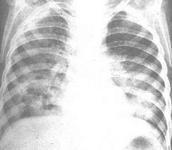

類鼻疽桿菌肺炎

• 類鼻疽桿菌肺炎

628健康網為您分享有關類鼻疽桿菌肺炎的癥狀,類鼻疽桿菌肺炎的治療方法,類鼻疽桿菌肺炎的預防知識,類鼻疽桿菌肺炎的癥狀...